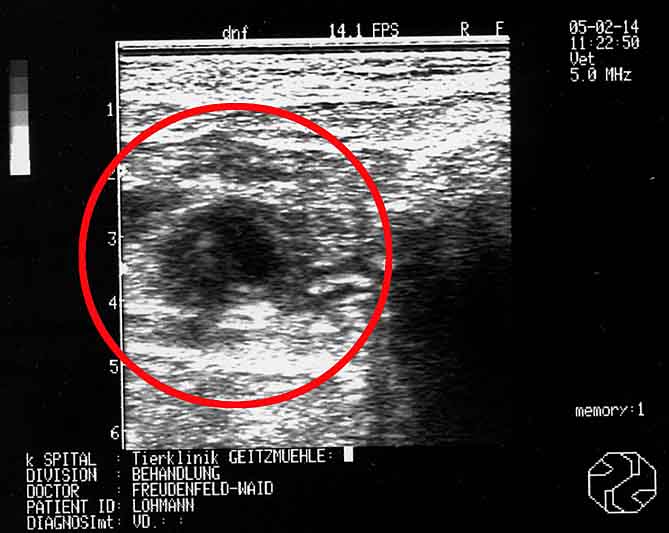

Schallbild vom 11.02.2005